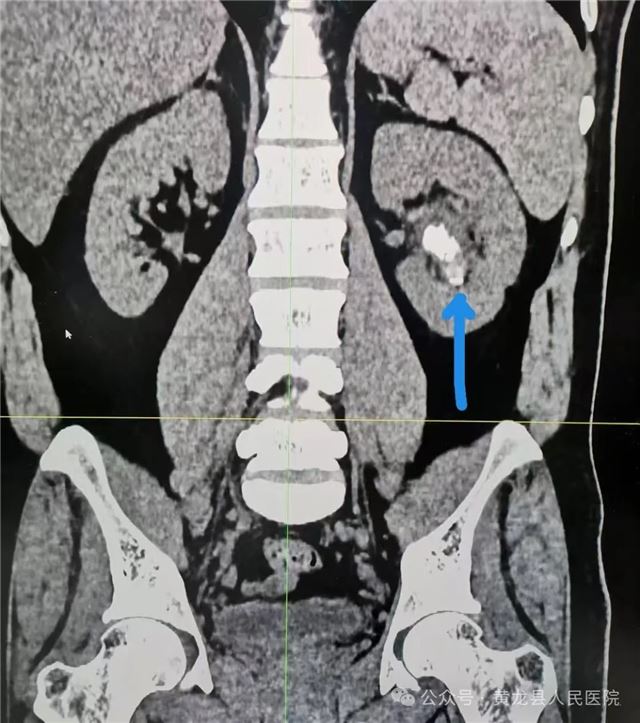

术前CT影像